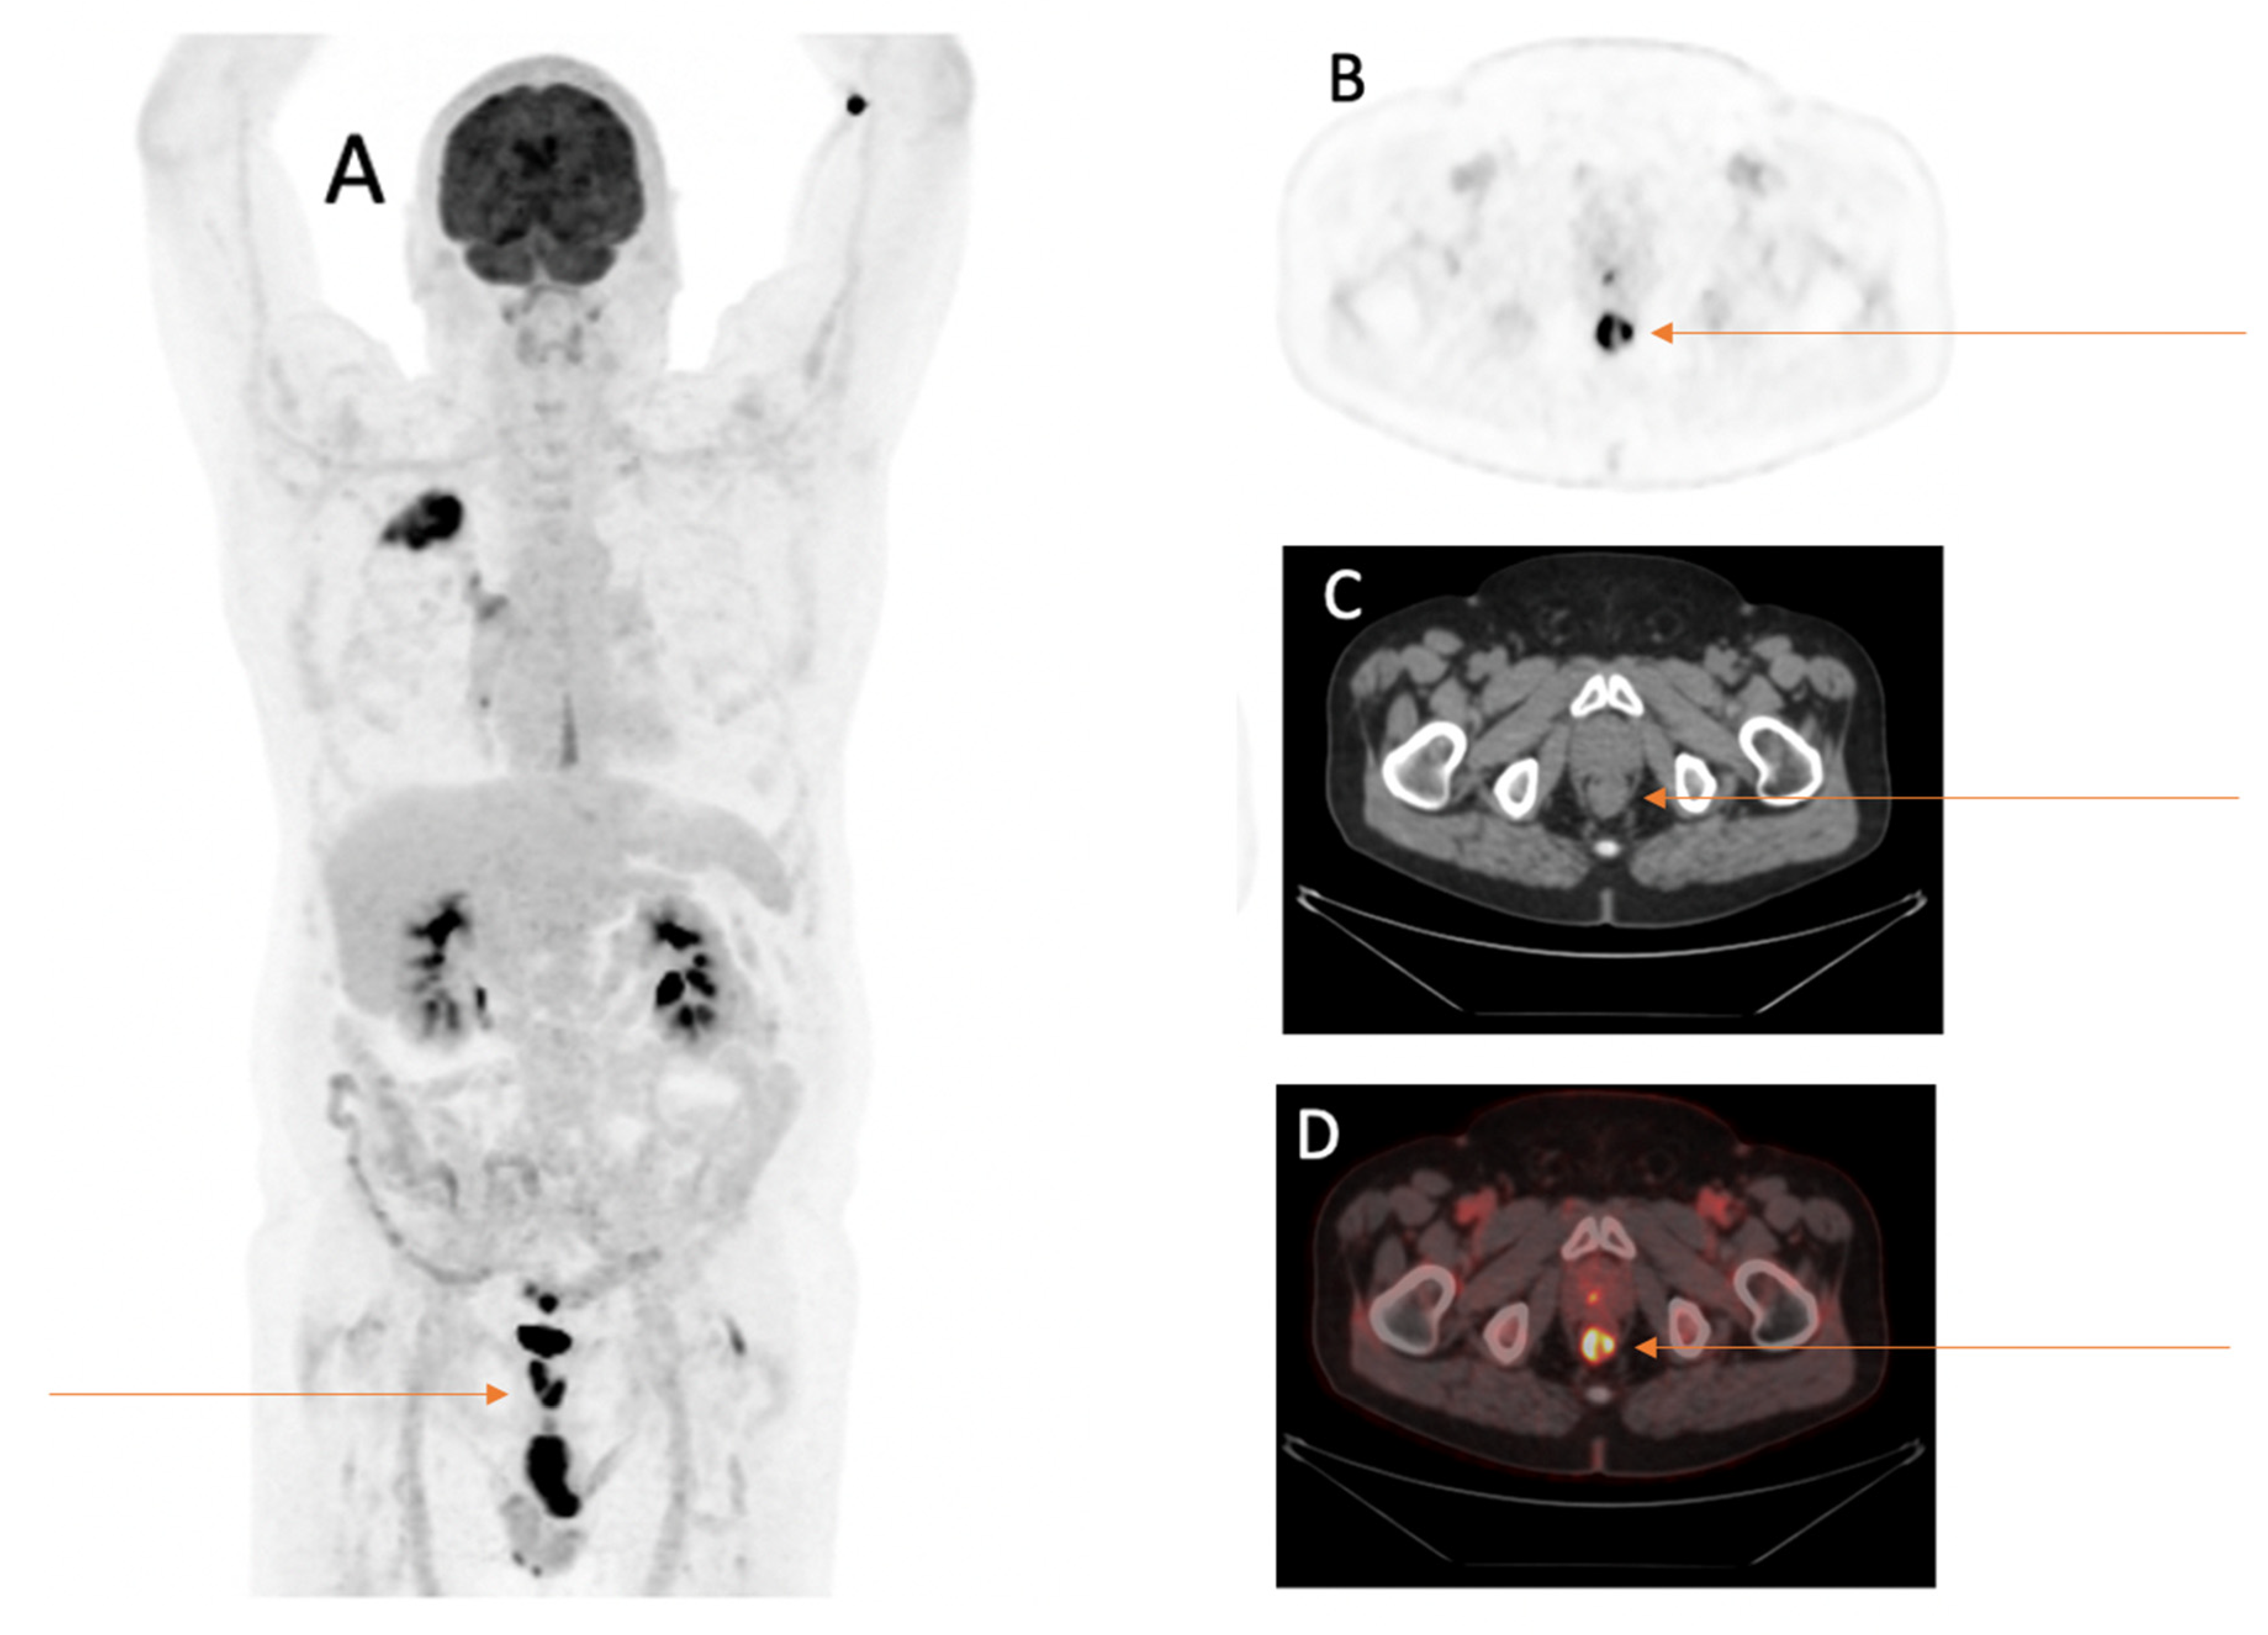

Additional Primary Tumors Detected Incidentally on FDG PET/CT at Staging in Patients with First Diagnosis of NSCLC: Frequency, Impact on Patient Management and Survival

3.4. Further Description of Suspicious Findings